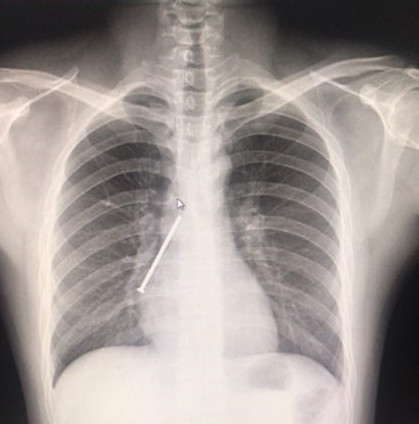

6月28日下午,王明在姐姐的陪同下,来到南方医院呼吸与危重症医学科求救。接诊的主任医师佟万成看到王明的胸片后,意识到情况非常危险,立马安排患者迅速完成必要的术前检查,并联系呼吸内镜中心为患者开通绿色通道。

经过该科室主任蔡绍曦和两个主任医师佟万成、刘来昱的研究,发现患者右下肺异常高密度铁钉样阴影较前并没有明显的变化,担心铁钉已经扎透气管壁,于是讨论制定了三套治疗预案,如有意外随时做好急诊开胸手术的准备。